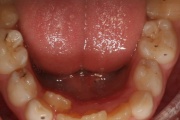

Keel